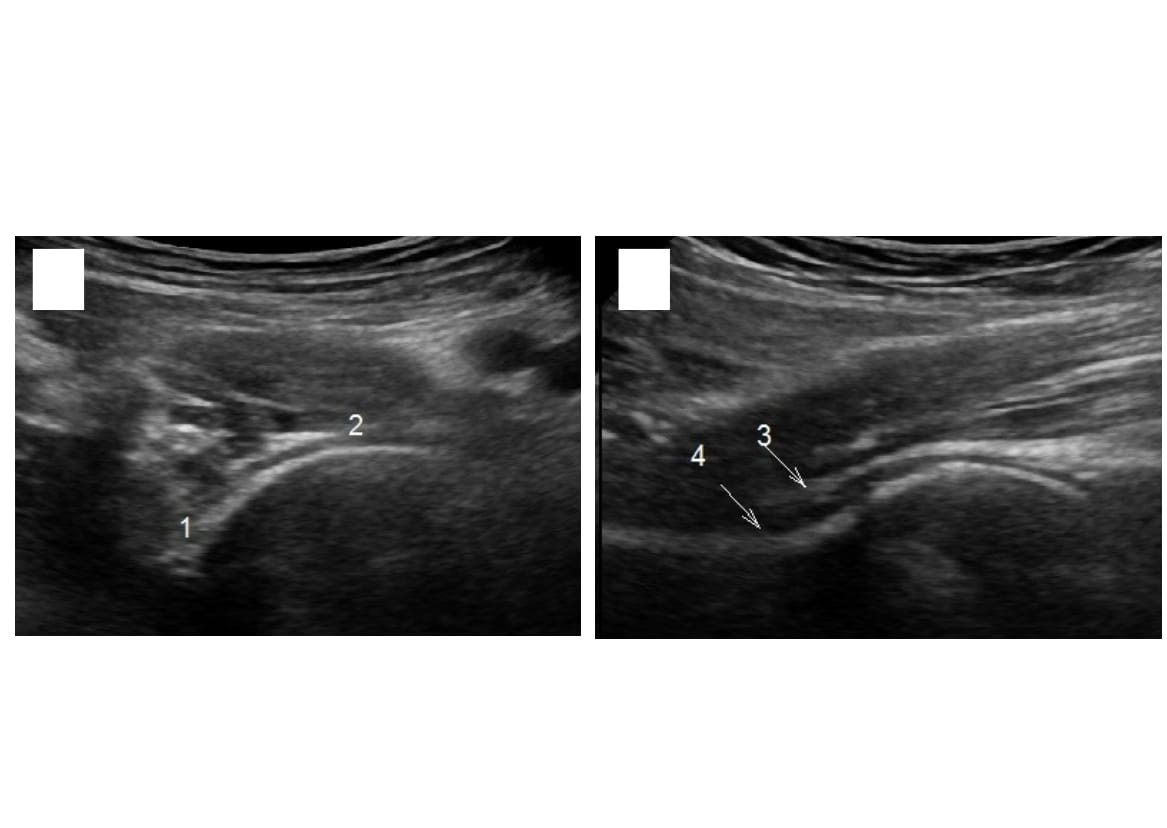

Normally, the Echographic evaluation of the hip joint visualizes the femoral head (FH) of spherical shape with an even uniform contour, with congruent surfaces of FH and acetabulum. Acoustic density of subchondral bone plate equals 187±11 conventional units (conv.un). Fibrous membrane of the joint capsule is determined as a homogenous strip of a high acoustic density, with 1.4±0.5 mm thickness. Synovial membrane of the capsule in healthy individuals, as a rule, has hypo-echogenic structure, and is 6.5±0.5 mm in size. Hyaline cartilage is 0.4±0.2 mm thick and has a regular uniform contour along the whole FH (Fig. 1).

Fig. 1. Sonograms of a healthy hip joint of a 27-year old patient

А – standardscanning 1 cmbelowPoupart’sligament: the head of spherical shape is visualized centered in the acetabulum, contour of the subchondral plate regularand uniform; 1 – head width (28 mm), 2 – joint gap (3.5 mm);

B – scanning along the femoral neck: 3 – fibrous membrane of the joint capsule (1.8-2.2 mm), 4 – synovial membrane of the capsule (4.6-5.0 mm), the joint capsule (6.8 mm)